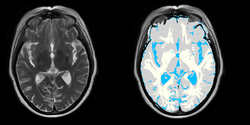

Brain Atrophy in HIV Patients

- Collaborator: David Tate, PI (Brigham and Women's Hospital), Troy Russel (Brigham and Women's Hospital), Alex Zaitsev (Brigham and Women's Hospital/Surgical Planning Laboratory) and National HIV Consortium

- Short description: Evaluate Brain Atrophy in HIV Patients

- Image specification: 3 Tesla, Scanner: NA, MPRAGE, Sagittal Scans, TR/TI/TE=NA, pixel_xsize = 0.9375, pixel_ysize = 0.9375, fov = NA, aspect = NA, space = 1.5

- Used Task: MRI Human Brain